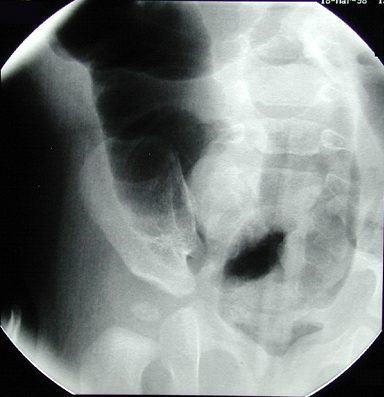

Diagnosis?

Intussusception